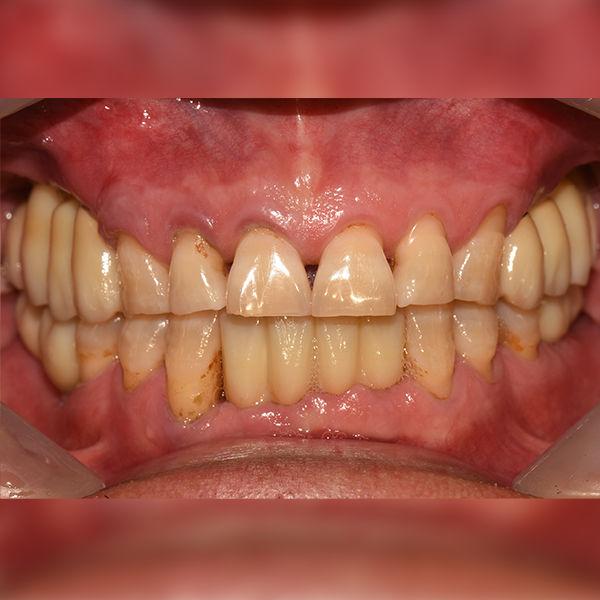

Тохиолдол.172 50-аад насны Ли*ган 2019-01-11 / 2019-07-24

Before Before

After After